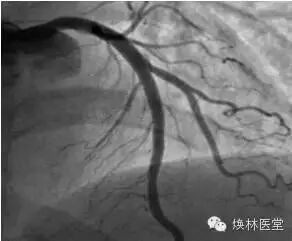

正常人的心脏血管的冠状动脉造影的图像如下:

我们再来看看他冠脉造影心脏的血管情况:

他的心脏血管三支病变,简单的说,就是冠心病比较严重。